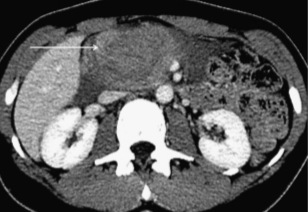

(Слева) На аксиальной КТ с контрастным усилением у пациента, получившего травму, определяется гематома на ограниченном участке в области перехода головки в шейку (спереди), наличие которой обусловлено ушибом. Разрывов поджелудочной железы не определяется.

(Справа) На аксиальной КТ с контрастным усилением визуализируется жидкость, окружающая поджелудочную железу Несмотря на то, что признаков разрыва поджелудочной железы на КТ выявить не удалось, наличие жидкости возле нее, особенно в сочетании с повышением сывороточного уровня липазы и амилазы, является крайне подозрительным признаком повреждения поджелудочной железы.